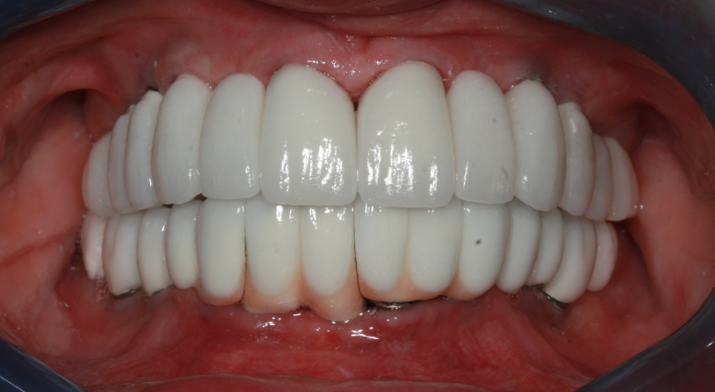

There are a wide variety of such interdental products on the market. For implant patients, the author recommends choosing an oral irrigator that pulsates and has at least two tips: the universal tip and the dental implant tip with three tufts. A Tufts University School of Dental Medicine study found a water flosser with implant tip was 145% more effective than string floss around implants when used in conjunction with a manual toothbrush.9 Significant reduction of gingival bleeding at 2 weeks and 30 days, respectively, were reported.9 Improvement in the health of tissues around implants can be seen in one patient who presented with inflammation around an implant (Figure 1), and another patient with a full-arch prosthesis that now has minimal-to-no plaque around both the top and bottom peri-implant tissues (Figure 2).

Full-arch prosthesis showing minimal-to-no plaque around both the top and bottom peri-implant tissues after oral irrigator use.

Figure 2